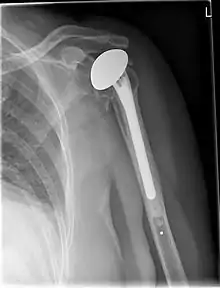

استبدال مفصل الكتف

جراحة استبدال مفصل الكتف هي عملية جراحية يتم فيها استعاضة مفصل الكتف (المفصل الحُقاني العضدي) كلية أو جزئياً بغرسة صناعية. وتجرى هذه الجراحات عامةً لتخفيف الآلام الروماتزمية الناتجة عن تآكل أسطح مفصل الكتف أو لعلاج الكسور الشديدة في منطقة الكتف.[1]